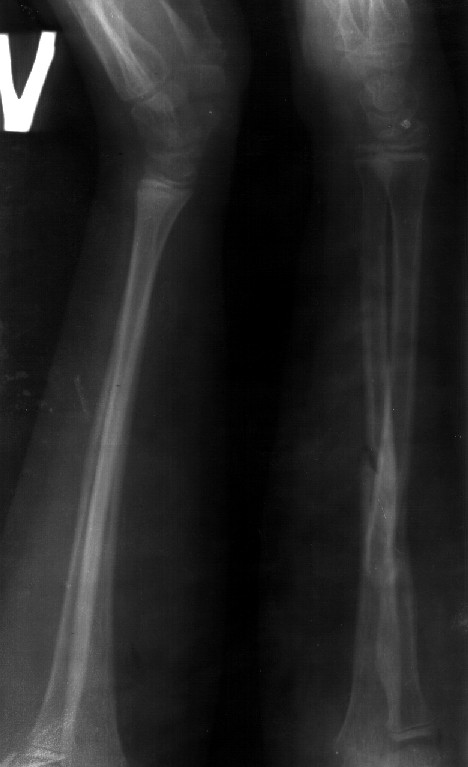

Сделал симметричные снимки с максимальной супинацией и пронацией при согнутом предплечье в 90 град. Объем ротационных движений 90-100 град.

Снимок один сделан с супинацией, второй - оба предплечья в одинаково нейтральном положении. то есть по этим снимкам объем ротационных движений не оценить. Снимко в двух проекциях лучше и делать в среднем положении между пронацией и супинацией, то есть обе проекции в однм и том же положении, когда линия, проходящая через шиловидные отростки, идет в плоскости головки. Прошу прощения за усложнение простых вещей.